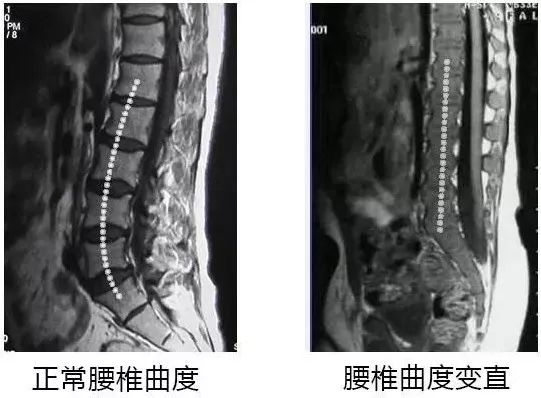

这种姿势让脊椎一直维持着“弓背”的状态

全身的重量全压在脊椎骨底端

一旦腰椎受到挤压,整个身体就变形了

腰椎间盘 变直,反弓